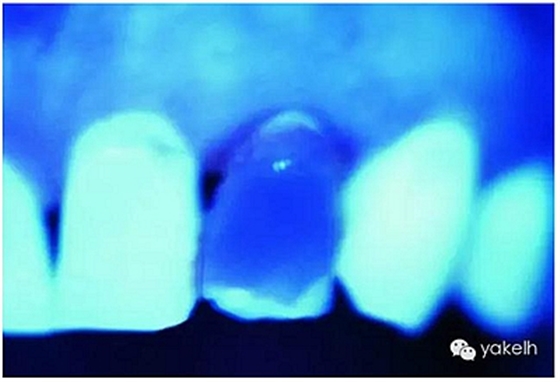

圖2.38用有熒光性的混合填料樹脂材料修復的修復體表現(xiàn)出和鄰牙渾然一體的亮度。

圖2.39修復體在紫外線光下顯示出極佳的熒光效應。